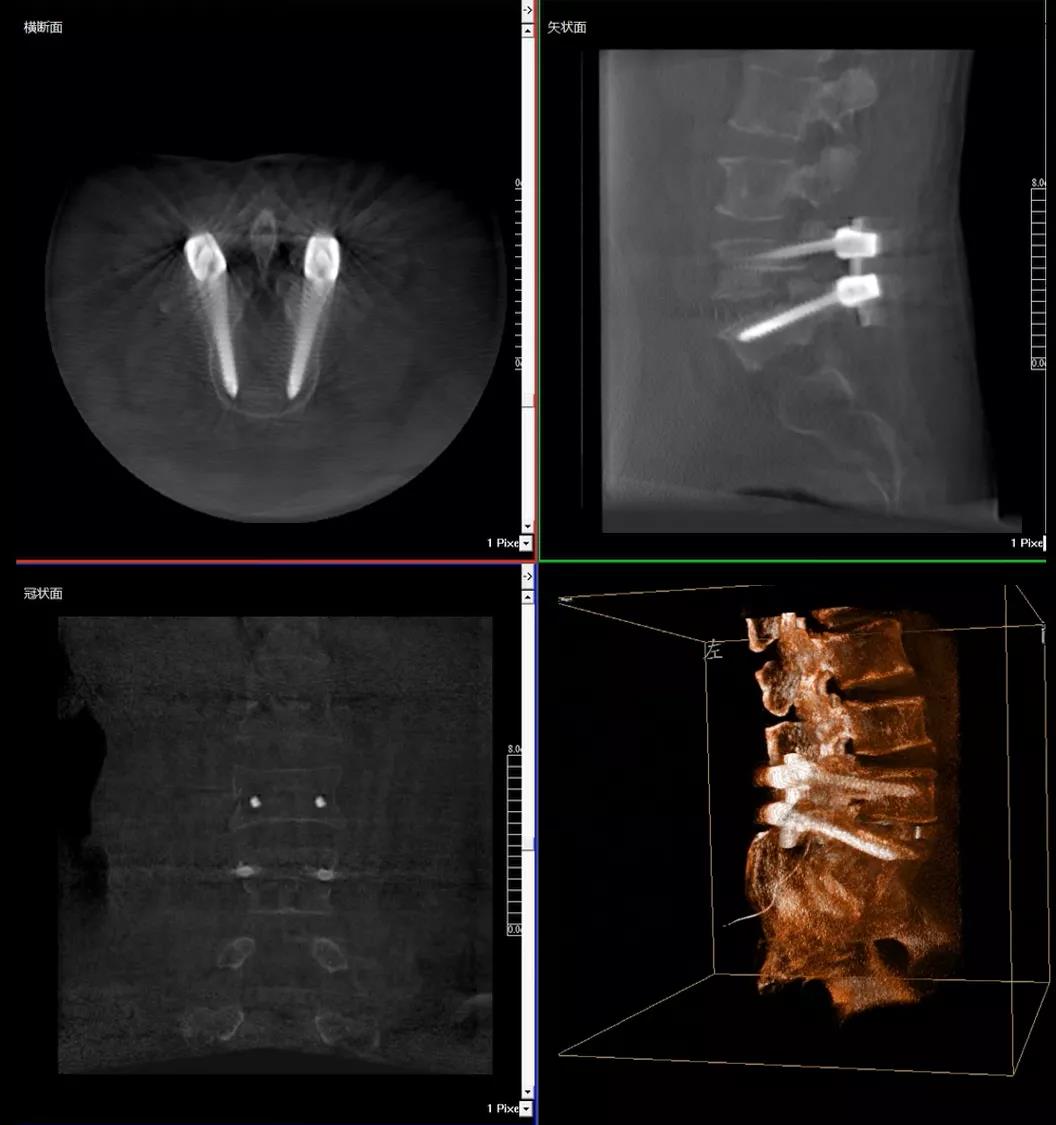

術(shù)中快速生成橫斷面、矢狀面、冠狀面斷層圖像和三維立體圖像